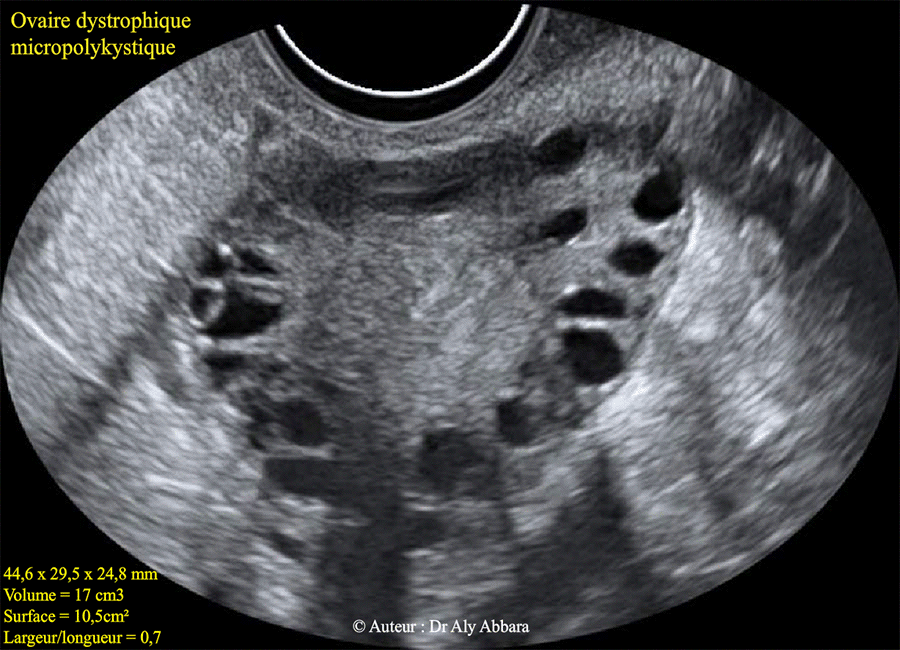

Ovaire dystrophique micropolykystique (OMPK)

Images échographiques d'un ovaire (gauche) dystrophique micropolykystique chez une femme âgée de 30 ans.

* Les caractéristiques échographiques de cette ovaire dystrophique :

- Dimensions : 44,6 x 29,8 x 24,8 mm

- Volume = 17 cm3

- Surface = 10,5 cm²

- index de sphéricité : rapport (largeur/longueur) = 0,7

- Nombre de follicule identifiables de 2 à 9 mm = 20

- Distribution périphérique des follicules

- Stroma central hypertrophique et hyperéchogène repoussant les follicules vers la périphérie.